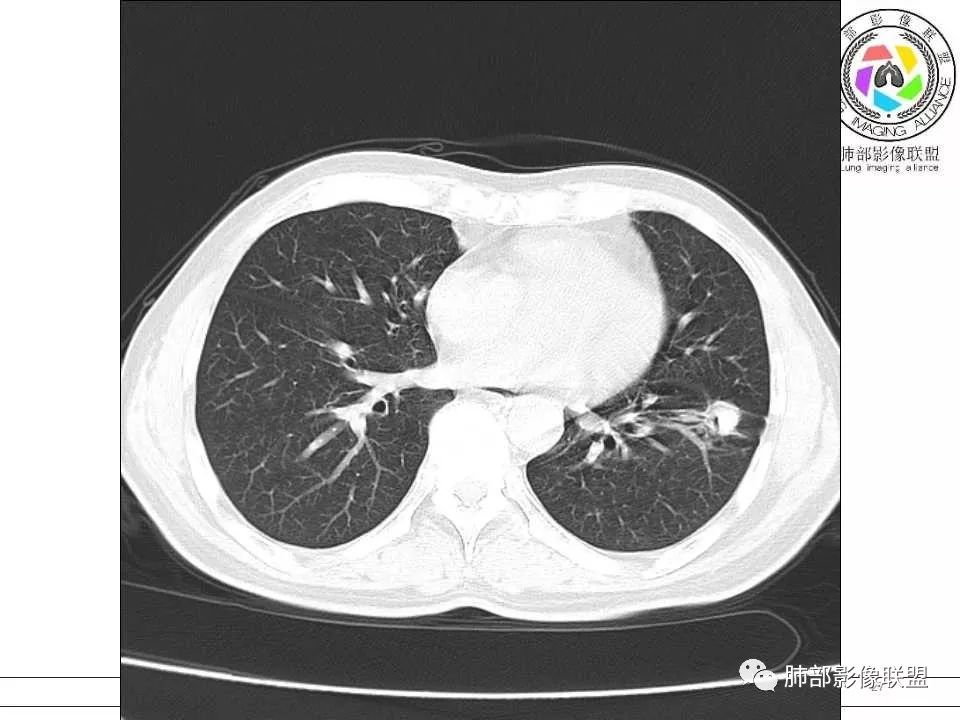

双肺弥漫小树丫,树丫边界清楚,右肺磨玻璃结节,病变包绕血管束,血管走形自然(考虑微浸润腺癌)。左肺下叶多发实性结节,结节以支气管血管束周围分布,大小均一,部分结节伴有空洞,洞壁内侧可见引流支气管及支气管壁增厚,洞壁外侧可见钙化,随访两个月有明显吸收,部分有残留小结节。中老年男性,无实验室检查。考虑:左肺炎性肉芽肿,结核,隐球,组织胞浆菌,NTM,建议完善实验室检查及支气管镜检查。 医学百科网 | YxBaike.Com

患者中年男性,咳嗽咳痰两周。胸部CT:右肺上叶尖段不规则混合磨玻璃结节,见分叶、毛刺及血管穿行征象。左肺下叶前基底段沿支气管血管束分布外大内小片状实变、磨玻璃及空洞影,空洞壁薄,见平直、钙化征象。4月多后复查胸部CT,右肺上叶病灶变化不大,左肺下叶病灶明显吸收,遗留部分结节灶。期间治疗方案不详。综合考虑右肺上叶腺癌可能性大(微浸润至浸润),鉴别结核。左下肺炎性病变,结核可能性大,鉴别小细胞癌。 医学百科网 | YxBaike.Com

右肺上叶混合性磨玻璃结节,边缘清晰,磨玻璃内可见多发小空泡,五个月后增大。左肺下叶空洞,周围多结节堆积。病灶见引流支气管,周围卫星灶。二元论:右肺上叶浸润性腺癌,左肺下叶结核。

右肺上叶混合磨玻璃结节,有分叶毛刺,复查有增大,高密度有增多,考虑肺腺癌。左肺下叶病灶,内见空洞且空洞内壁光滑,周围见花花草草,复查部分病灶有吸收,考虑炎性病变,结核? 医学百科网 | YxBaike.Com

中年男性,咳嗽咳痰2周。CT:1.左下肺主病灶近圆形结节,内见空洞、钙化,周围索条、实变影,5个月后主病灶没有明显变化,周围病灶似有减少,考虑陈旧性病变;2.右上肺混合磨玻璃结节,见移动联通血管,边缘磨玻璃影边缘清楚,5个月后结节增大,考虑恶性肿瘤——IAC。 医学百科网 | YxBaike.Com

中年男性,咳嗽、咳痰2周。CT:1.左下肺主病灶类圆形结节,内见空洞,有引流支气管,周围索条、实变影,4个月后主病灶没有明显变化,周围病灶变化不大,考虑慢性炎性病变,TB?2.右上肺mGGN,实性成分不规则,血管进入,病灶边缘清楚,4个月后结节增大。考虑:腺癌,MIA? 医学百科网 | YxBaike.Com

右上叶磨玻璃结节,边清,分叶,5个月进展,似有变大,实性成分增加。左下肺内前底段结节及周围渗出,内有钙化,5个月吸收缩小。意见:右肺IAC,左肺TB。

右肺上叶混合磨玻璃结节,边缘清晰,分叶,血管进入稍增粗,隐约小空泡,约5月复查密度稍增高,考虑LPA;左肺下叶结节,新月形厚壁空洞,引流支气管稍增粗,钙化,周围树芽征,复查病灶变小,考虑结核。 医学百科网 | YxBaike.Com

中年男性。第一次CT右肺上叶后段mGGN,边缘GGO边界清楚,其内血管影杂乱扭曲。左肺下叶前内基底段结节,边界清楚,其内见粗糙钙化,近肺门侧见空洞,似与近端支气管相通,并支气管壁似有增厚,周围见卫星灶、树芽征、纤维条索及胸膜牵拉征,临近叶间胸膜轻度增厚牵拉移位。4个多月后复查,右肺上叶结节实性成分似有增多,病灶似有增大。左肺下叶病灶明显缩小。考虑右肺上叶后段肺癌,腺癌可能性大(MIA或IAC);左肺下叶前内基底段结核。

右肺上叶磨玻璃结节,边界清晰,内可见血管穿行,复查后病灶明显增大,实性成分增多,考虑腺癌。另左肺下叶病灶,内可见空洞伴钙化,周围可见散在卫星灶及索条,复查后病灶缩小,考虑结核。

右肺上叶后段混合磨玻璃结节,边界清晰,短毛刺、分叶,小叶阻挡,其内血管增粗、迂曲,考虑腺癌(IAC)。左肺下叶前基底段结节,可见厚壁空洞,内壁光整,可见引流支气管,壁可见钙化灶,边缘可见长毛刺、胸膜牵拉,周围卫星灶,考虑结核。

右上肺腺癌,左下肺结核 医学百科网 | YxBaike.Com

当肺部有结核或炎性背景时,如果肺部某一区域出现孤立性的GGO结节或实性结节的时候,一定要警惕:一是需要仔细分析孤立性GGO或实性结节的影像特征,看结节边界GGO是否清楚?周围是否有卫星灶等?结节内血管改变?是否有增粗或结构扭曲?是否有空泡征,胸膜凹陷?结节收缩力?毛刺分叶征等等。二是必要时结合治疗后复查,对照结节的大小,密度,形态等改变再一步分析。三是需要按肺部结节指南进行随访。一定不能忽视!